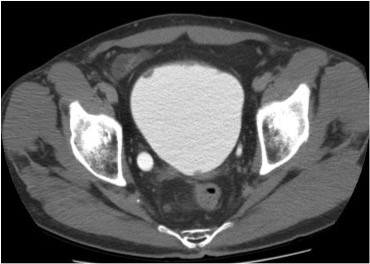

Se realiza nueva TC bifásico abdominopélvio y Uro TC.

CONCLUSIÓN:

- Paciente con numerosas recidivas por Cá vejiga.

- Ha desarrollado un tumor metacrónico en pelvis renal derecha, también responsable de la hidroureteronefrosis.

- Mala evolución radiológica del proceso a expensas de metástasis pulmonares y hepáticas.